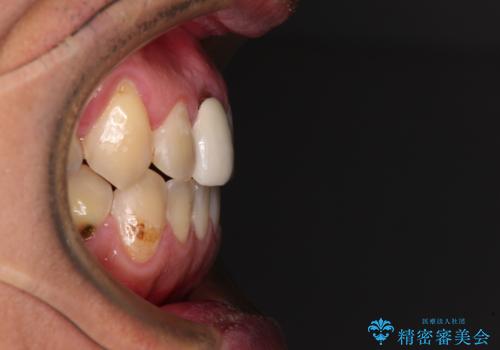

前歯のデコボコとクロスバイトをインビザライン矯正で改善

- 前歯のデコボコと上下のクロスバイトを気にして来院された患者様です。

インビザラインを用い、IPR(歯と歯の間を削る)と歯列全体を拡大させることで、歯並びを整えていくこととしました。

上の前歯が下の前歯を乗り越える際、奥歯がほとんど咬めない時期があり、乗り越えた後も、インビザライン特有の奥歯の咬みにくさが続きました。

咬み合わせ改善のために治療期間を要しましたが、最終的に奥歯はしっかりと咬めるようになりました